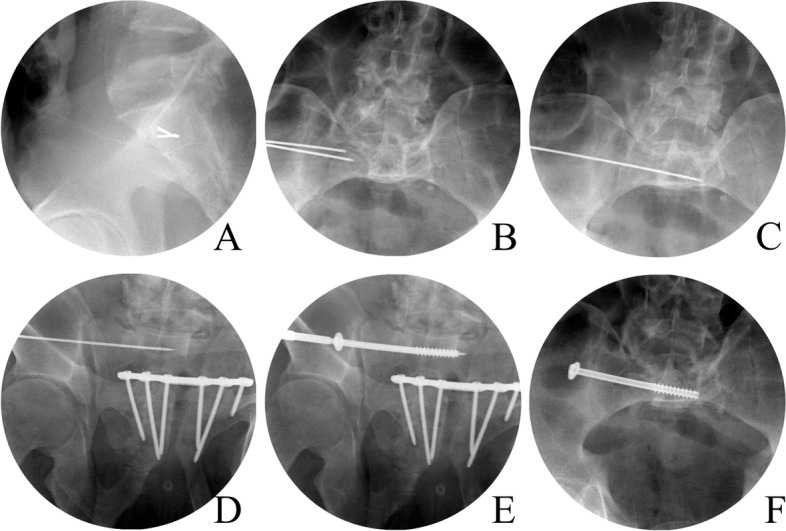

The patients were placed in a supine position on a transparent surgical table. A pad was placed under the lumbar region, and a small incision (1 cm) was made after identifying the safe zone on the lateral side of the pelvis. A guidewire was inserted through the safe zone and confirmed with C-arm inlet and outlet views [4, 8]. After confirming that the cannula was inserted through the incision as far as the ilium, the cannula was positioned parallel to the upper portion of the S1 vertebra along the superior margin under C-arm guidance. The guidewire was inserted from the ilium through the sacrum cross the middle of sacral body carefully so that it did not breach the sacral foramina, anterior and posterior to the cortex of the sacral body. Following Kirschner wire insertion, cannulated drill holes were made and 7.0- or 7.3-mm cannulated screws were introduced. If the fracture was considered highly unstable, the screws were inserted in the S2 vertebra in the same manner. The details of process for surgical technique of IS screw fixation is shown in Fig. 2.

Fig. 2.

The IS screw fixation technique on C-arm images. A The guidewire was inserted through safe zone confirming with C-arm lateral view. B the guidewire was advanced through outer, inner cortex of ilium, and sacrum outer cortex. C The position of guidewire was confirmed in pelvis inlet view, and D outlet view. E Inserted screw was checked to avoid violation of S1 foramen on pelvis outlet view. F screw breach in AP direction was checked on pelvis inlet view